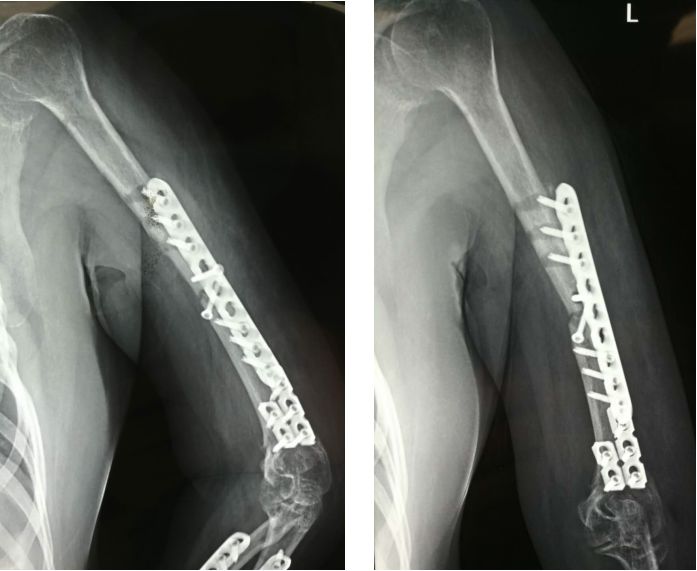

此处应用钢板有两种情况一是不会使用髓内固定,设备条件达不到;再就是理念落后见的病例少,交流少。此处外侧全部是长应力,钢板为张力钢板,内收肌力量强大,目前的钢板不能承受反复的弯曲应力,金属疲劳断裂失败率高,以下病例切开,钢丝捆绑进一步骨膜剥离,破坏了原始血肿,干扰骨愈合,都是失败原因

补救办法:剥削植骨髓内钉固定或动力髁钢板固定。

补救比较好